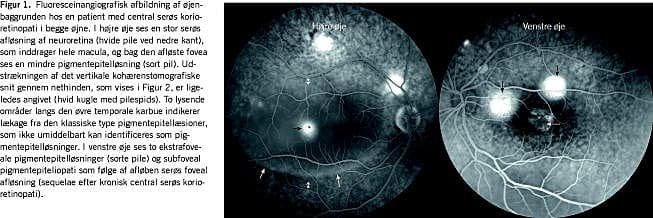

Central serøs korioretinopati (CSC) er en akut indsættende, undertiden asymptomatisk og kronisk forløbende øjensygdom, der er karakteriseret ved ophobning af klar væske mellem neuroretina og retinas pigmentepitel (Figur 1 ) [1]. Væskeansamlingen ses i relation til svær fokal angiografisk lækage af fluorescein, en markørsubstans, der vidtgående følger bevægelsen af vand gennem pigmentepitelet ind i lakunen mellem dette og den afløste neuroretina.

Typisk ved et nyligt udviklet førstegangstilfælde af CSC er en prominerende bulløs afløsning af nethinden med klar væske foran pigmentepitelet, begrænset til øjets bagerste pol (Figur 1 og Figur 2). Fluoresceinangiografi viser en enkelt eller nogle få læsioner med ekspanderende lækage. Oftalmoskopisk ses der ofte en grynet aflejring bag nethinden [8].

Kronisk CSC har en fladere afløsning end akut CSC, og kan ofte kun diagnosticeres med OCT [9]. Angiografisk ses der et broget billede med uregelmæssig hyperfluorescens uden sikre identificerbare foci for lækage (Figur 1 og Figur 2).